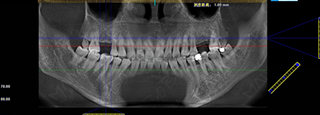

许女士术前口腔全景片